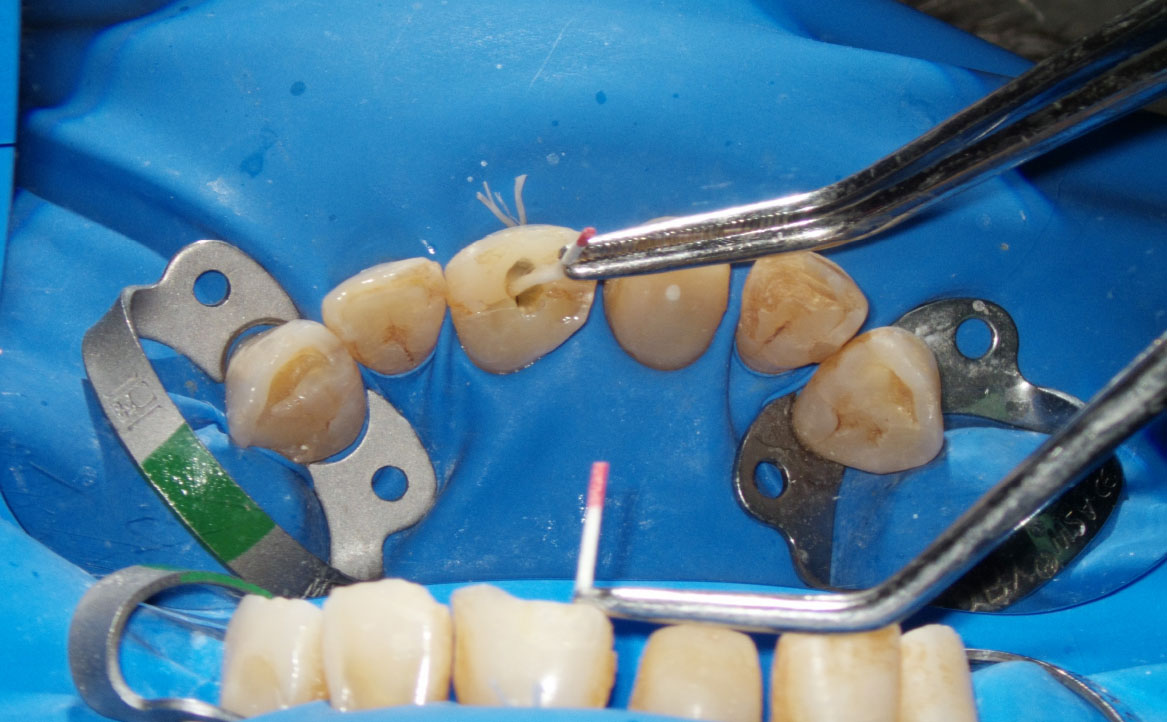

La specifica tip, che viene collocata all’interno della camera pulpare insieme all’irrigante (fig. 6), genera coppie di impulsi (ultra-short, 25µs) in grado di generare delle bolle: durante il collasso della bolla generata dalla prima irradiazione, viene emesso un secondo impulso in grado di generare una seconda bolla, che va a causare un ancor più rapido e violento collasso della prima. Il susseguirsi di questi collassi genera un’onda d’urto negli irriganti, capace di potenziare l’azione di disinfezione del canale (fig. 7). In altre parole, le bolle secondarie sono in grado di esercitare una pressione sulle prime tale da causare turbolenti moti degli irriganti in aree più profonde del sistema canalare, risultando così più efficaci della tecnica PIPS o delle tecniche di attivazione ad ultrasuoni in termini di eliminazione di detriti o smear layer, nonché in termini di capacità di penetrazione nei canali laterali (9).